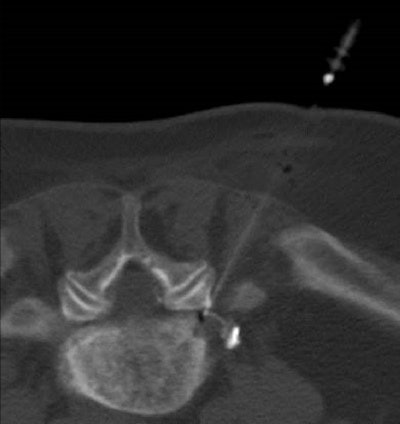

X-rays provide a very clear image of skeletal structures, while MRI can provide a picture of the physical-chemical condition of organs and this in turn allows for very precise specialist diagnostics. This means that the actual source of the pain -- the spinal column, musculature, or nerves -- can be identified very clearly. Such precision is impossible using only x-rays, as illustrated by the fact that the elderly are constantly undergoing skeletal changes that are very clearly seen on an x-ray, but their pain is not always consistent with such changes and this raises a key question.